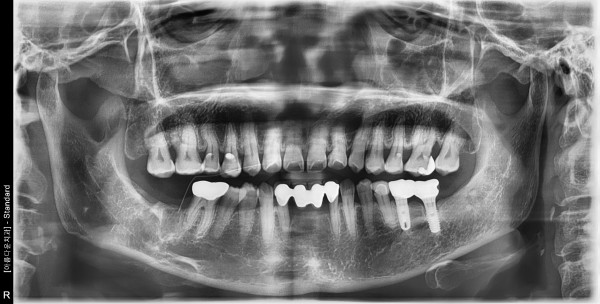

58세 여자 하악 우측 구치부 기존 임플란트 픽스쳐 제거 후 치조골이식술, 임플란트 식립